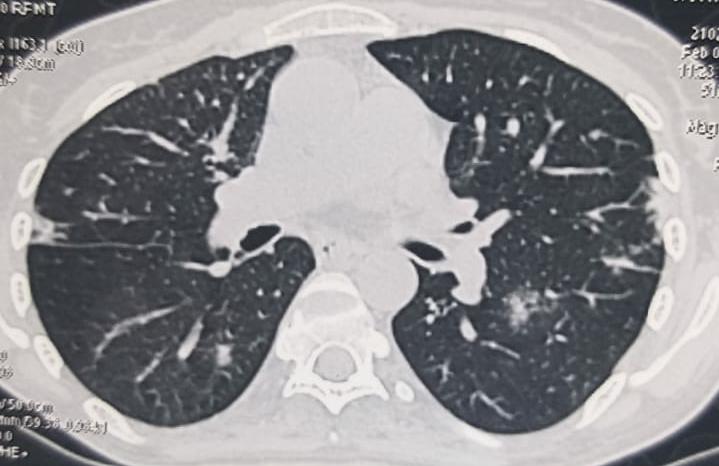

Ankylosing spondylitis is a chronic inflammatory disease affecting the young men and less commonly women with a spectrum of manifestations including uveitis, arthritis, sacroiliitis, colitis and psoriasis (spondyloarthropathy). Mixed connective tissue disorder (MCTD) is a complex and heterogenous autoimmune disease that affects women in their childbearing age. It is characterized by circulating autoimmune antibodies that deposit in tissues, resulting in inflammatory response, causing irreparable tissue damage. Overlap and co-existence of these diseases are uncommon, as per literature evidence. The present study has reported the case of a 35-year-old female, who had HLA B27-positive spondyloarthropathy for 10 years and had been receiving sulfasalazine, and had neck swelling for 4 months. Screening conducted for TB in view of fever, weight loss and neck nodes, had reported negative results. She was found to have Reynaud’s disease, arthritis, bilateral cervical lymphadenopathy and elevated autoantibody titers including ANA, U1SM/RNP and Coombs-positive hemolysis. The diagnosis was concluded as MCTD and she had responded well to the treatment. As per the available literature, this could be touted as the first case study of a female patient with ankylosing spondylitis and MCTD.